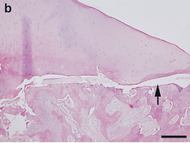

Остеохондроз (от греч. οστεον — кость и χόνδρος — хрящ) — комплекс дистрофических нарушений в суставных хрящах. Может развиваться практически в любом суставе, но чаще всего поражаются межпозвоночные диски. В зависимости от локализации выделяют шейный, грудной и поясничный остеохондроз. Следует обратить внимание на то, что в англоязычной медицинской литературе термином osteochondrosis обозначают совершенно другую группу ортопедических заболеваний, которые в русском языке называют остеохондропатиями.